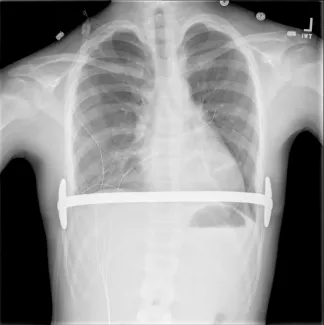

Repair with a metal pectus bar, called the Nuss Procedure, is achieved by bending a stainless bar to fit the chest wall. The bar is then inserted and secured through a small incision under each arm using the aid of a endoscope to monitor and avoid injury to the heart during insertion. The bar goes over the ribs and under the sternum, to push the sternum forward into the new position. The ends of the bar are secured to the chest wall. This procedure takes between 1–2 hours.